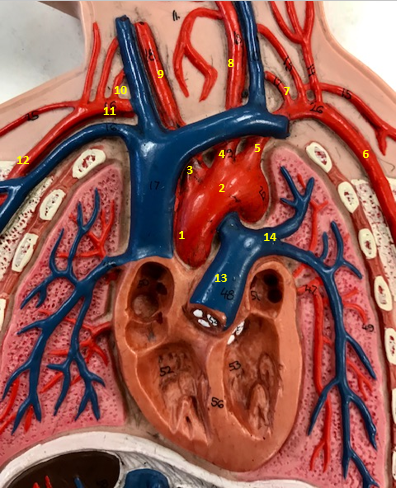

Aorta

Name #2

Brings blood out of left ventricle

Function of aorta

Brachiocephalic artery

Name #3

Supplies oxygenated blood to right arm shoulder neck and head

Function of brachiocephalic artery

Left common carotid artery

Name #4

Supplies oxygenated blood to left neck and head

Function of left common carotid artery

Left subclavian artery

Name #5

Supplies oxygenated blood to left arm shoulder

Function of left subclavian artery

Left axillery artery

Name #6

supplies blood to left armpit and upper limb

Function left axillary artery (6)

Left vertebral artery

Name #7

Supplies blood to brain and spinal cord

Function of left vertebral artery (7)

Left common carotid artery

Name #8

Supplies blood to left neck and head

Function of left common carotid artery (8)

Right common carotid artery

Name #9

Supplies oxygenated blood to right neck and head

Function of right common carotid artery (9)

Right vertebral artery

Name #10

Supplies blood to brain and spinal cord

Function of right vertebral artery (10)

Right subclavian artery

Name #11

Supplies blood to right arm and shoulder

Function of right subclavian artery

Right axillery artery

Name #12

Supplies blood to right armpit and upper limb

Function of right axillery artery (12)

Pulmonary trunk

Name #13

Bring blood out of right ventricle to lungs

Function of pulmonary trunk (13)

Left pulmonary artery

Name #14

Bring blood to left lung

Function of left pulmonary artery (14)